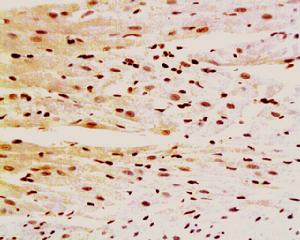

(2)光學顯微鏡檢查:可見心肌細胞肥大,胞核變小,數目減少,部分心肌細胞橫紋消失,細胞間隙和血管周圍纖維增生。

(3)電子顯微鏡檢查:可見心肌細胞受損,線粒體、肌漿網腫脹、空泡化,肌纖維內含有大量脂類。值得指出的是不論肉眼或顯微鏡觀察,本病與擴張型心肌病,均無特殊差別。